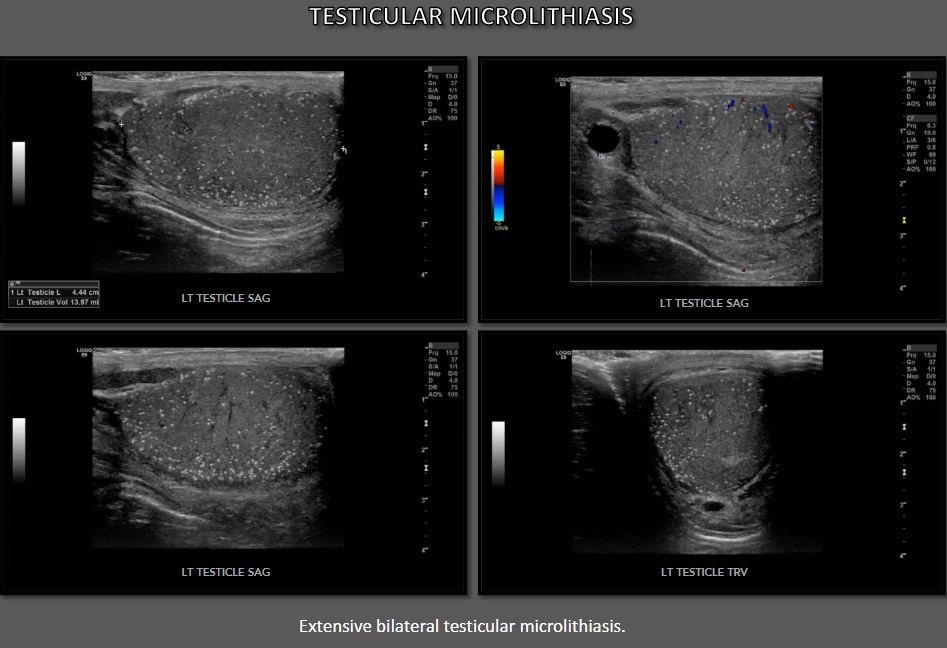

첫 번째 초음파 설명은 다음과 같습니다. 1987년에 “무수한 작은 밝은 메아리가 확산되고 균일하게 울립니다. 물질 전체에 흩어져 고환의.” 그 이후로 많은 수의 다양한 설명과 정의 를 설정하는 데 사용되었습니다. 고환 미세 결석 진단. 가장 보편적으로 받아들여지는 정의는 5개 이상을 포함합니다. 단일 필드당 관찰되는 미세석 초음파에서 보기(이미지). 미세석 현재 상태와 관련된 작고 같은 크기(<3mm) 에코 발생 후방 그림자가 없는 초점 고환 전체에서 관찰됩니다. 고전적인 초음파이지만 고환 미세 결석증의 발현 확산, 마이크로리스는 고환의 일부가 보고되었습니다.

반짝이는 인공물은 평가할 때 볼 고환 미세 결석 컬러 도플러 초음파. 마이크로리스의 수 이미징에서 감지된 내용은 다를 수 있습니다. 상당히. 조건 로 등급이 매겨졌다 최소/약함(등급 I: 5~10 microliths), 중간 (등급 II: 10 내지 20 마이크로리스), 및 중증(등급 III: >20 마이크로리스)에 따라 미세 석회화 수 단일 보기에서 볼 수 있습니다.